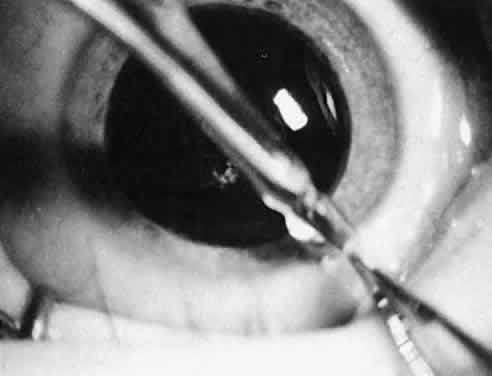

Not all cataracts require surgical treatment. Eyes with punctate or small anterior polar cataracts and others with partial opacification of the lens, such as posterior lenticonus, which only slightly interferes with the refraction of light, are best followed and not surgically treated (Fig. 1). In some cases, it is difficult to determine whether the presence of a partial cataract is responsible for a decrease in visual acuity or whether the refractive error or optical distortion produced by the cataract has produced a mild, reversible form of deprivation amblyopia. In these situations, correction of the refractive error and a trial of occlusion therapy should be attempted. If the visual acuity improves, it may be deduced that amblyopia was responsible for the loss of visual acuity and that the optical distortion produced by the partial cataract is not yet surgically significant.

Usually, anterior polar cataracts are visually insignificant and allow normal visual development (see Fig. 1). However, some affect vision, and all require careful monitoring.7 Centrally located cataracts that are on or near the posterior lens capsule have a greater effect on the refraction of light and visual acuity (Fig. 2). Nuclear cataracts associated with metabolic disorders or prenatal infections produce double refracting systems that cause optical distortion and significantly decrease visual acuity (Fig. 3).